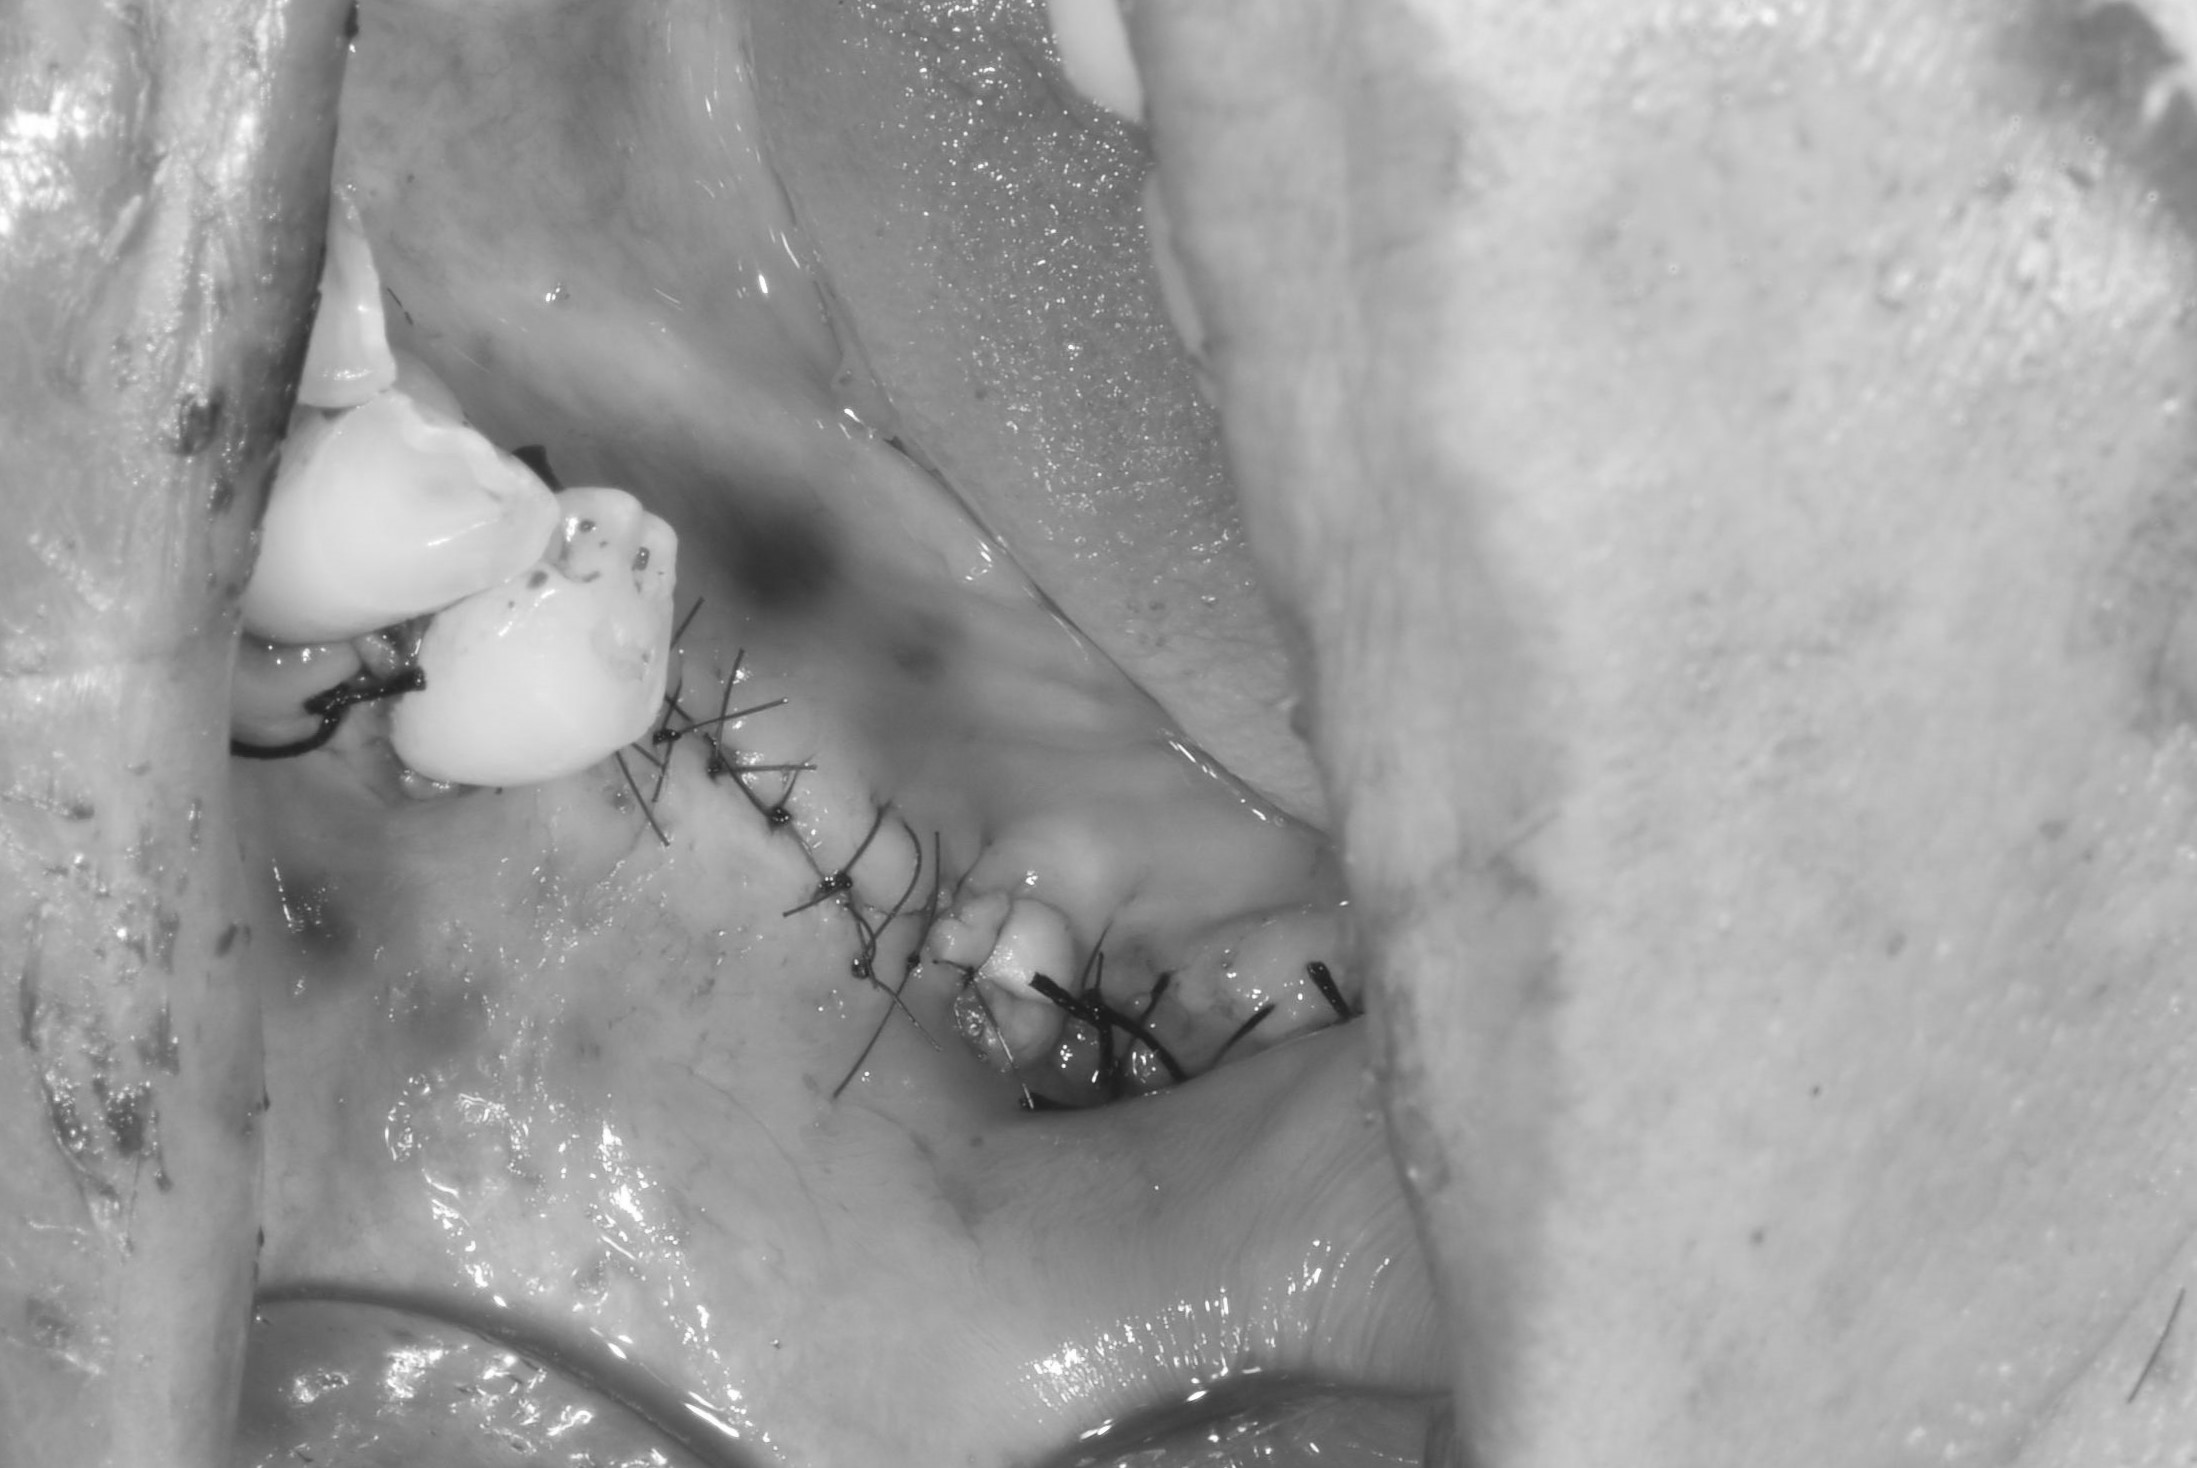

案例二

補入所需的骨粉

完成後依骨頭恢復裝況,需定期回診給醫生評估是否進行下一個階段